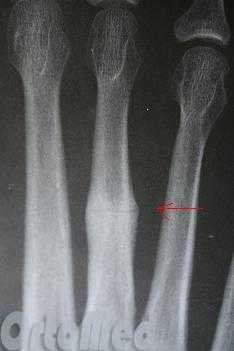

Рентгенограмм в 2-х проекциях обычно достаточно, чтобы диагностировать перелом. Но при стресс-переломах без смещения, иногда, их невозможно определить даже очень опытному врачу.

В таких случаях назначаются контрольные рентгенограммы через 10-14 дней, когда происходит резорбция костной ткани в месте перелома. Так же стресс переломы трудно увидеть на рентгеновских снимках, пока они не начали срастаться и не начала образовываться костная мозоль. Как раз её очень хорошо видно на рентгенограммах. Компьютерная томография или МРТ могут быть необходимы для исключения стресс перелома и других патологий стопы.